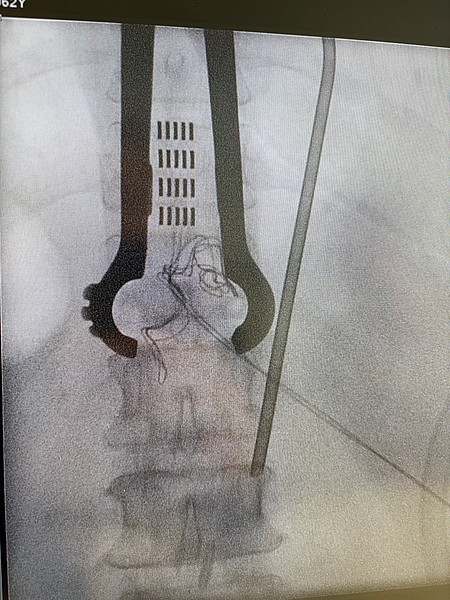

Spinalganglienstimulation („dorsal root ganglion“-Stimulation)

Neben der Rückenmarksstimulation ist es bei bestimmten chronischen Schmerzen möglich, ganz gezielt bestimmte Spinalganglien zu stimulieren. Das Spinalganglion ist ein Bündel aus Nervenkernen und Nervenfasern, das alle sensorischen und schmerzhaften Reize einer Nervenwurzel verarbeitet. Bei diesem Verfahren werden feine Elektroden direkt an das Spinalganglion eingesetzt. Wie bei der Rückenmarksstimulation werden die Elektroden durch einen Impulsgeber angesteuert, der unter die Haut implantiert wird. Die abgegebenen elektrischen Impulse hemmen die Schmerzweiterleitung. Diese Therapie findet Anwendung bei thorakalen Neuropathien (z.B. nach Mastektomie, Thorakotomie oder Herpes Zoster), bei Leistenschmerzen nach Leistenhernienoperationen, bei Schmerzen nach Operationen am Knie, Fuß, Hüft Hand oder Schulter sowie beim komplexen regionalen Schmerzsyndrom oder Phantom- und Stumpfschmerzen nach Amputationen. Auch bei der Spinalganglienstimulation bleiben die Nervenstrukturen erhalten, sodass die Stimulation jederzeit rückgängig gemacht werden kann. Die Einstellungen des Impulsgebers lassen sich von außen – auch durch die Patient:innen – verändern, sodass die Stimulation jederzeit an die Bedürfnisse der Patient:innen angepasst werden kann.